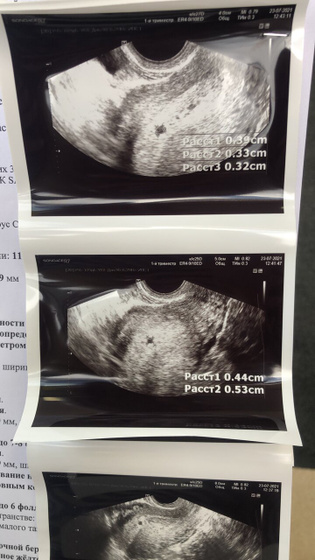

И на фото пя очень маленькое. Сколько мм в диаметре ?